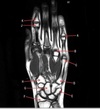

What is letter A?

BASE OF 2ND METACARPAL

74

What is letter B?

TRAPEZOID

75

What is letter C?

CAPITATE

76

What is letter D?

SCAPHOID

77

What is letter E?

RADIUS

78

What is letter F?

ULNA

79

What is letter K?

LUNATE

80

What is letter G?

TRIQUETRIUM

81

What is letter H?

HAMATE

82

What is letter J?

BASE OF 5TH METACARPAL